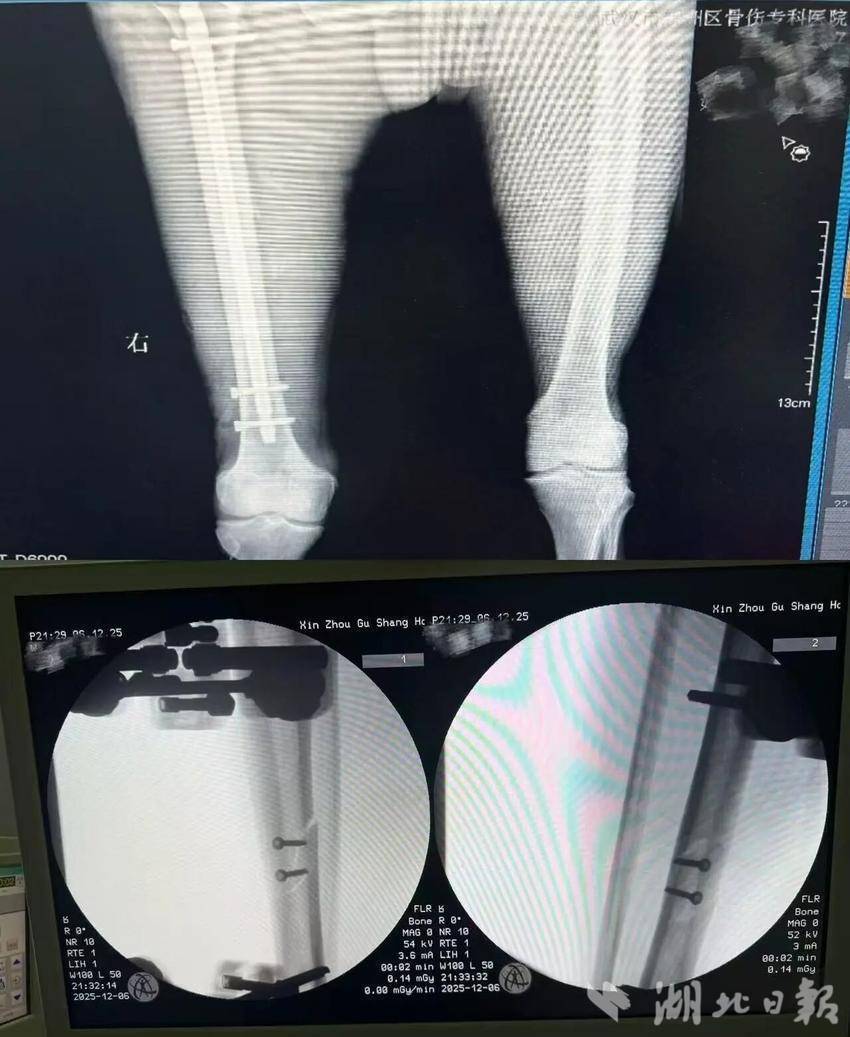

经DR与CT全面排查,初步诊断的“开放性胫骨骨折”仅为表层伤情,患者实际伤情更为危重:右下肢开放性胫骨骨折、股骨干骨折,双侧多发肋骨骨折(左侧8根)伴创伤性气胸,第5腰椎及多处横突骨折,且合并多年高血压病史,身体耐受度差,需立即启动紧急救治方案。

救治团队首先全力稳定患者生命体征,排除手术禁忌。随后,手术团队凭借精湛的显微外科技术,为患者实施右胫骨清创、血管神经吻合等一期手术,在显微镜下精准吻合断裂的大隐静脉,为肢体血供恢复筑牢基础。一周后,患者伤情稳定,团队顺利为其完成股骨干骨折二期内固定术。